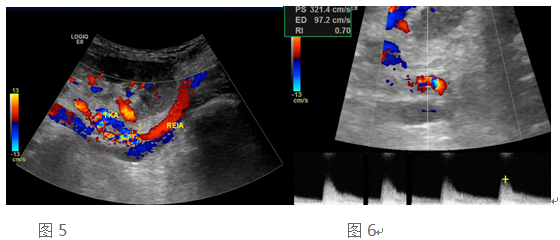

41岁的陈先生,因尿毒症在外院行同种异体肾移植手术,术后肌酐升高三个月,入住我院移植科。常规移植肾术后超声发现:移植肾形态未见异常,移植肾动脉吻合口血流信号呈五彩镶嵌(图5),吻合口血流速度明显升高(图6),符合移植肾动脉吻合口狭窄。